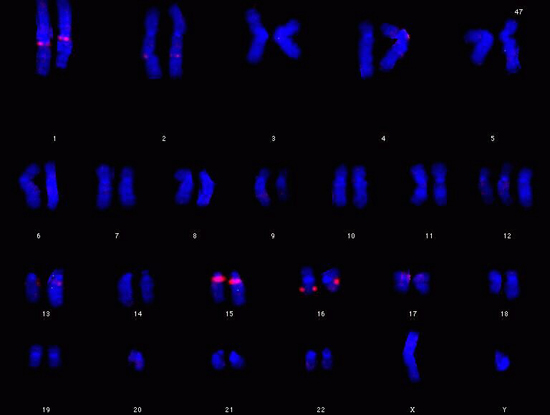

Obesità infantile: un gene mancante nel cromosoma 16 tra le cause genetiche

In particolare, lo studio rivela che “uno specifico gene sul cromosoma 16, chiamato SH2B1, gioca un ruolo fondamentale nel regolare la fame, il peso e i livelli di zucchero nel sangue”. Si tratta della “prima evidenza di una mutazione genetica collegata a un problema metabolico come l’obesita’”, precisa Hurles. Secondo i ricercatori la scoperta puo’ avere anche implicazioni diagnostiche, contro un problema sempre piu’ epidemico tra i ‘figli’ delle societa’ occidentali.